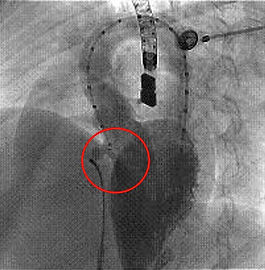

Aparece en el círculo la comunicación interventricular.

Se aprecia defecto interventricular muscular medial.